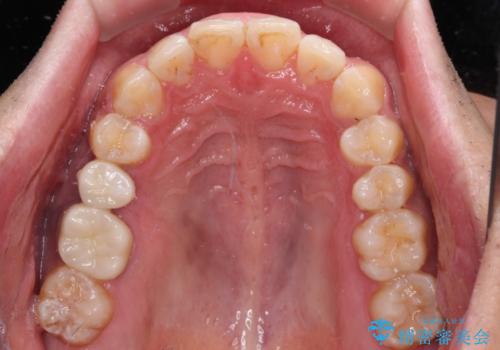

- 上下前歯部の叢生を気にして来院された患者様です。

レントゲン撮影により、右上奥歯が折れていることが分かりました。

患者様自身も何となく違和感を覚えていたとのことで、インプラント補綴治療を行うこととしました。

歯列不正は比較的軽微であったので、インビザラインによる矯正治療とし、矯正治療中にタイミングを見て抜歯とインプラント埋入を行う予定としました。